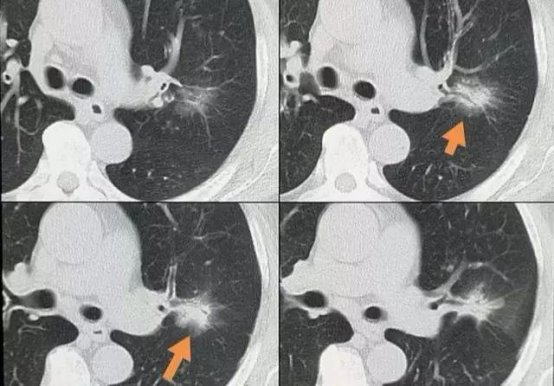

在杭州某体检中心的影像科,副主任医师王琳指着屏幕上的毛玻璃结节说:“这个4毫米的病灶,放在五年前可能就被漏诊了。”如今,1毫米级精度的低剂量CT让早期肺癌无所遁形:

山东省立医院影像科主任吴敏的诊室里,常年备着速效救心丸:“太多人看到报告上的『结节』就崩溃,其实80%的肺结节是良性的。”她总结出恶性结节的五大特征:

形态不规则:边缘毛刺状或分叶状

密度不均:混合磨玻璃密度(实性成分>50%)

生长迅速:半年内体积倍增

血管穿行:CT增强可见血管进入病灶

位置特殊:靠近胸膜或支气管